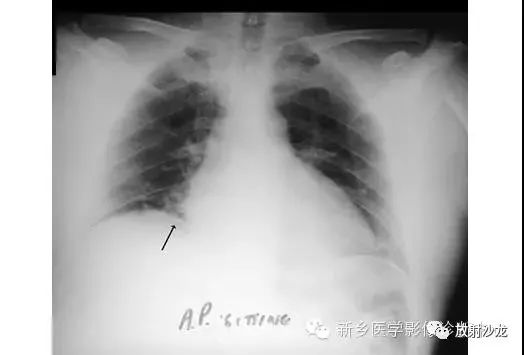

同一患者前-后坐位的胸片所示右膈下(箭头)游离气体,证实了气腹的诊断。